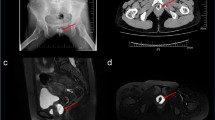

Diagnosis can be achieved using retrograde contrast studies, CT scan, or MAG3 renography

Radical cystectomy and urinary diversion is the gold-standard treatment for muscle-invasive and high-risk non-muscle-invasive bladder cancer. Ureteroenteric anastomotic stricture is a well-known complication of urinary diversion and is associated with serious sequelae that lead to total or partial loss of kidney function, infectious complications, and the need for additional procedures. Although the exact aetiology of benign ureteroenteric anastomotic strictures is unclear, they most likely occur secondary to ischaemia at the anastomotic region. Diagnosis can be achieved using retrograde contrast studies, CT scan or MAG3 renography. Open revision remains the gold-standard treatment for ureteroenteric anastomotic strictures; however, endourological techniques are being increasingly used and, in select patients, might be the optimal approach.